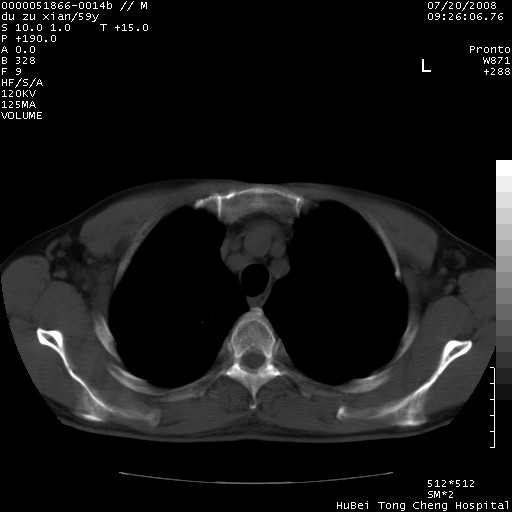

以下是引用宇宙ct在2008-8-25 23:21:00的发言:[br]右肺周围性肺癌并肋骨转移,纵隔淋巴结转移。

以下是引用zsl6918在2008-8-25 22:40:00的发言:[br]右肺周围性肺癌并肋骨转移,纵隔淋巴结转移。

以下是引用zy_zj在2008-8-26 15:24:00的发言:[br]单从病变本身,我倾向良性炎性病变,但肋骨转移了,所以说是考虑右肺周围性肺癌并肋骨、纵隔淋巴结转移可能性大。